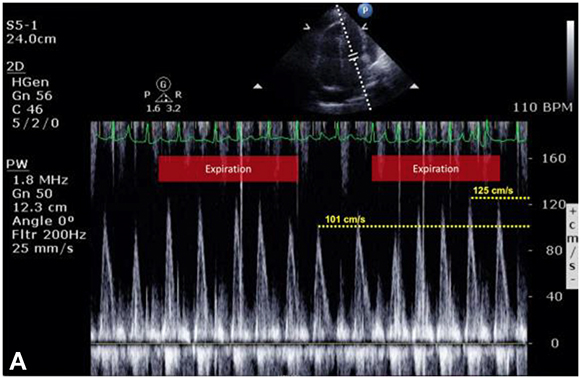

Figure 12.8.: Exaggerated Ventricular Interdependence.

Exaggerated ventricular interdependence. A and B show pulsed-wave Doppler interrogation of transmitral and transtricuspid velocities obtained during a transthoracic echocardiographic study in a patient with suspected cardiac tamponade. The patient is breathing spontaneously; although there is no respirogram on the original images, the patient's marked sinus arrhythmia clearly defines inspiratory and expiratory phases. During negative pressure inspiration, A demonstrates a 25% decrease in transmitral E-wave velocities, whereas B shows a more than 45% increase in transtricuspid E-wave velocities. This exaggerated, reciprocal change in ventricular filling is a hallmark of cardiac tamponade and constrictive physiology. C shows an apical four-chamber view of this patient's heart, demonstrating a large effusion outside the right and left ventricles as well as a deep pool surrounding the right atrium (RA) (labeled by asterisks). Although not evident on this still image, interventricular septal "bounce" was prominent.